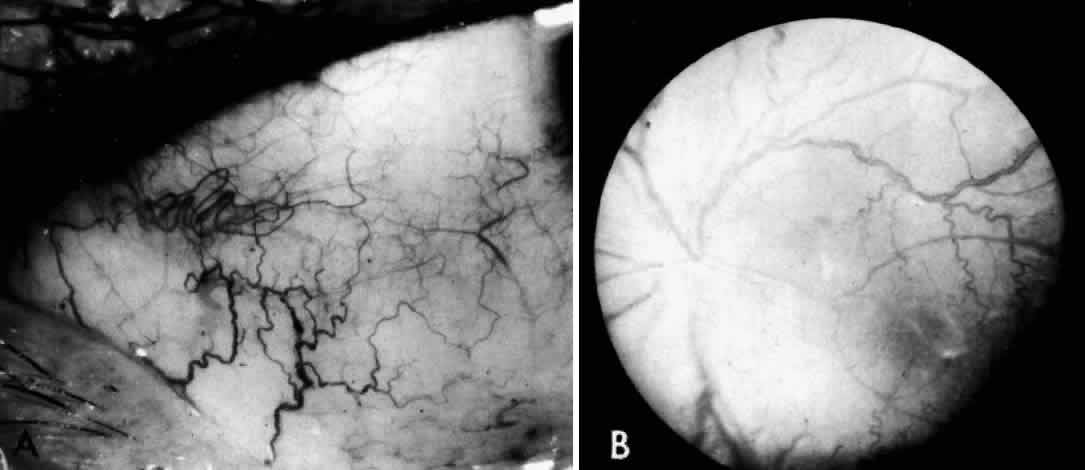

Electron microscopic examination of the cornea and retina showed the lipid stored was in the form of membranous cytoplasmic bodies (Fig. 7).68 The distribution of these inclusion bodies is similar to that of the birefringent material seen on light microscopy. The bodies are most abundant in retinal ganglion cells and retinal pigment epithelium. They are present in moderate numbers in corneal stromal cells, lens epithelium, corneal endothelium, vascular endothelium, and the sphincter muscle of the iris. They are infrequent in Müller cells, glial cells, and rod and cone inner segments.

Fig. 7. Retinal ganglion cell. (A) Portion of cell in Niemann-Pick disease, showing numerous membranous cytoplasmic bodies. Mitochondria (m) and dilated endoplasmic reticulum (er) are also evident. Area outlined in lower right is shown in greater magnification in B. (× 15,000) (B) Portion of cytoplasm of ganglion cell shown in A. Membranous cytoplasmic bodies cut in several different planes are evident, as are mitochondria (m) and endoplasmic reticulum (er) (×42,000). (Robb RM, Kuwabara T: The ocular pathology of type A Niemann-Pick disease: A light and electron microscopic study. Invest Ophthalmol 12:366, 1973)

The morphology of the membranous cytoplasmic bodies found in the eye in Niemann-Pick disease type A corresponds closely to the previously reported ultrastructure of lipid inclusions in the brain and viscera in other patients with Niemann-Pick disease type A. An ocular ultrastructural study of a 23-week-old fetus with Niemann-Pick disease type A also demonstrated rather extensive ocular involvement.69